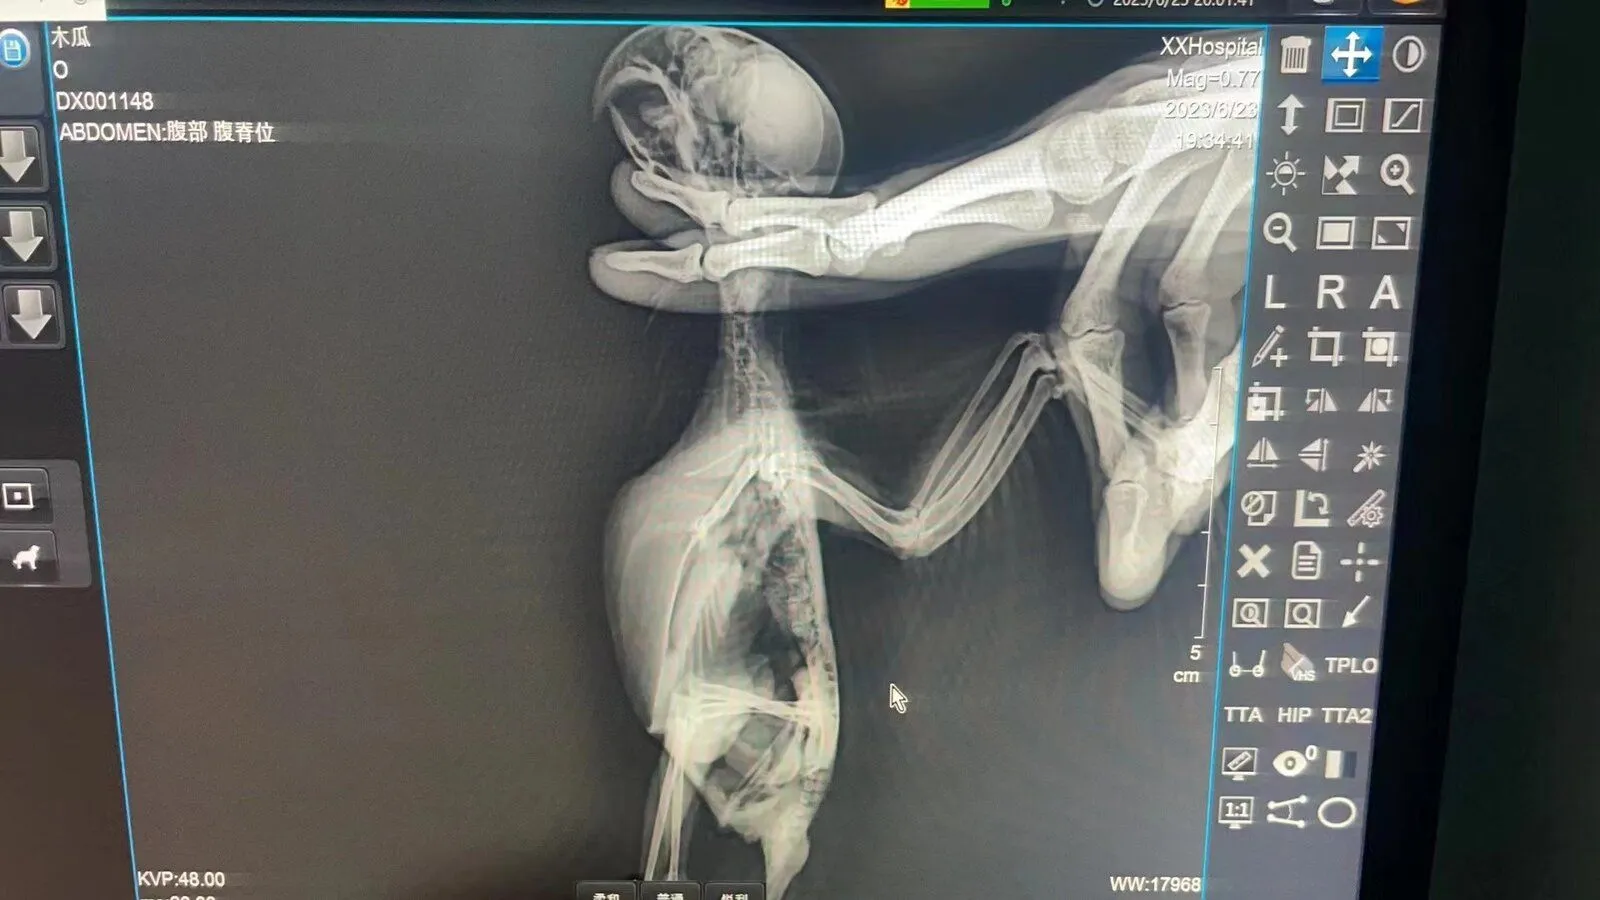

Update some pictures of the test......Pawpaw's bones are alright but stomach is bleeding. Hope he will get better!View attachment 51922View attachment 51923View attachment 51924